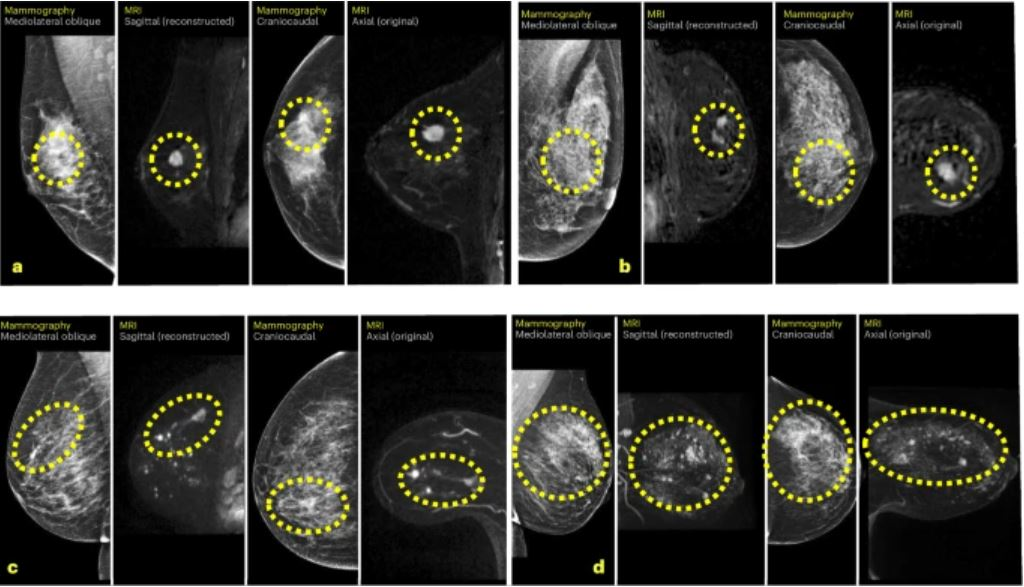

Another AI-related article posted this week focuses on a new study from the Karolinska Institute in Sweden. The authors found that using an AI-based score to select a small proportion of women for supplemental MRI after negative mammography detected many missed cancers.